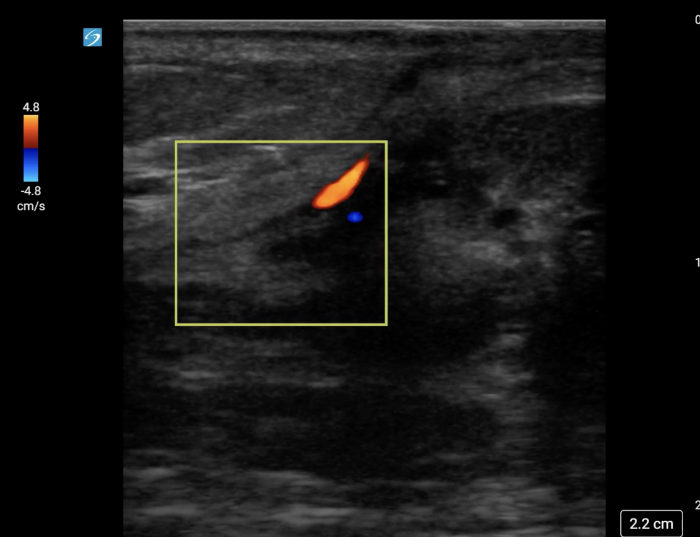

In your first image (Image 1), you realize there is no flow with color Doppler. Additionally, you find a torsed cord complex (Image 2), also known as the “corkscrew sign.” You consult Urology who is busy in the operating room with another case. You decide to perform a manual detorsion due to your concern for testicular atrophy and risk of infertility. Using the open book technique, you get relief of pain and return of vertical positioning of the testicle after two rotations. On your repeat testicular POCUS with color Doppler you obtain these images (Images 3 and 4), which demonstrate venous and arterial flow throughout the testicle. The cord is now untwisted and appears linear in orientation.

Torsion - image 4_crop.pngImage 4. Linear, untwisted appearance of the spermatic cord with accompanying vessels.